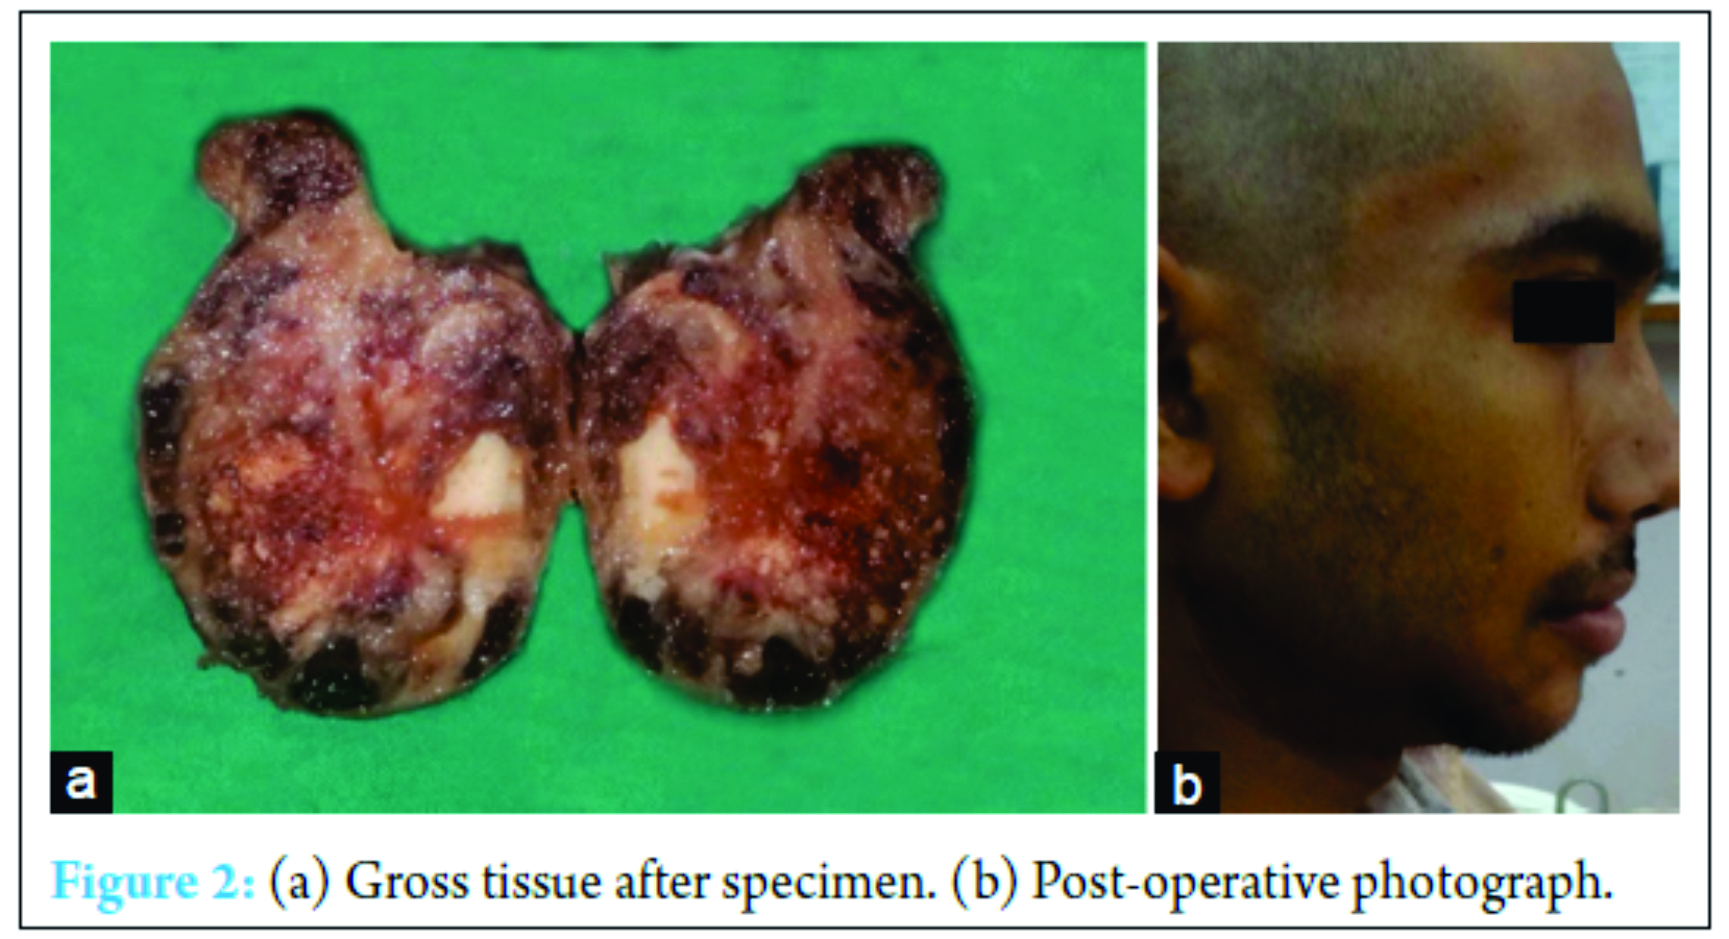

Radiographic evaluation included panoramic radiograph, occlusal radiograph, and cone beam CT. Panoramic radiograph revealed an ill-defined mixed radiolucent and radiopaque lesion along the right side of body of mandible denoting irregular areas of osteolysis (Fig. 1c). The cross-sectional occlusal radiograph of the right side of body of mandible showed bicortical expansion and presence of radial spicules which spread outside the lingual side of jaw bone giving sunray appearance (Fig. 1d). Aspiration was done which gave yellowish viscous blood tinged fluid. Based on clinical and radiological findings, the provisional diagnosis of malignancy of right side of the mandible, hemangioma, and osteosarcoma was given. The incisional biopsy revealed osteoid tissue with irregular trabeculae with osteoblasts which were large round to oval, epithelioid in appearance with hyperchromatic nucleus and prominent nucleoli and occasional atypical mitoses. Intertrabecular areas showed solid cellular stroma. As the biopsy was incisional, tumor border cannot be traced. Hence, the diagnosis was given as aggressive osteoblastoma/Osteoblastoma like osteosarcoma(Fig. 3b). Lesion was excised. Grossly, there was extensive soft tissue destruction with an associated soft tissue mass (Fig. 2a). The histopathology revealed abundance of osteoid and tumor bone without osteoblastic rimming suggestive of osteoblastic osteosarcoma (Fig. 3c). Other areas showed fibrous spindle cell areas where osteoid or tumor bone was scarce i.e. (fibroblastic/fibrohistiocytic type Fig. 3a). At focal places, vessels were numerous, dilated and proliferating giving a haemangiopericytomatous appearance (Fig. 3d) (Staghorn type appearance).

Osteosarcoma is an uncommon condition with an unusual presentation showing various histopathological patterns. This creates problems in correct diagnosis. Clinical appearance and radiology do not help in identification of the histopathological variant of osteosarcoma. Hence, histopathological examination of the fragments from all parts must always be done as the type of osteosarcoma may affect the treatment and the prognosis. In the present case, patient has no complaints to date (2 years post-surgically) (Fig. 2b). Follow-up intervals were every 6 weeks to 3 months in years 1 and 2; later, patient will be followed every 2-4 months in years 3 and 4, every 6 months in years 5-10, and every 6-12 months thereafter. Each visit will include a history and physical examination and a chest X-ray. X-rays of the primary tumor site are recommended every 4 months until the end of year 4. Late metastases may occur >10 years after diagnosis, and there is no universally accepted stopping point for tumor surveillance.